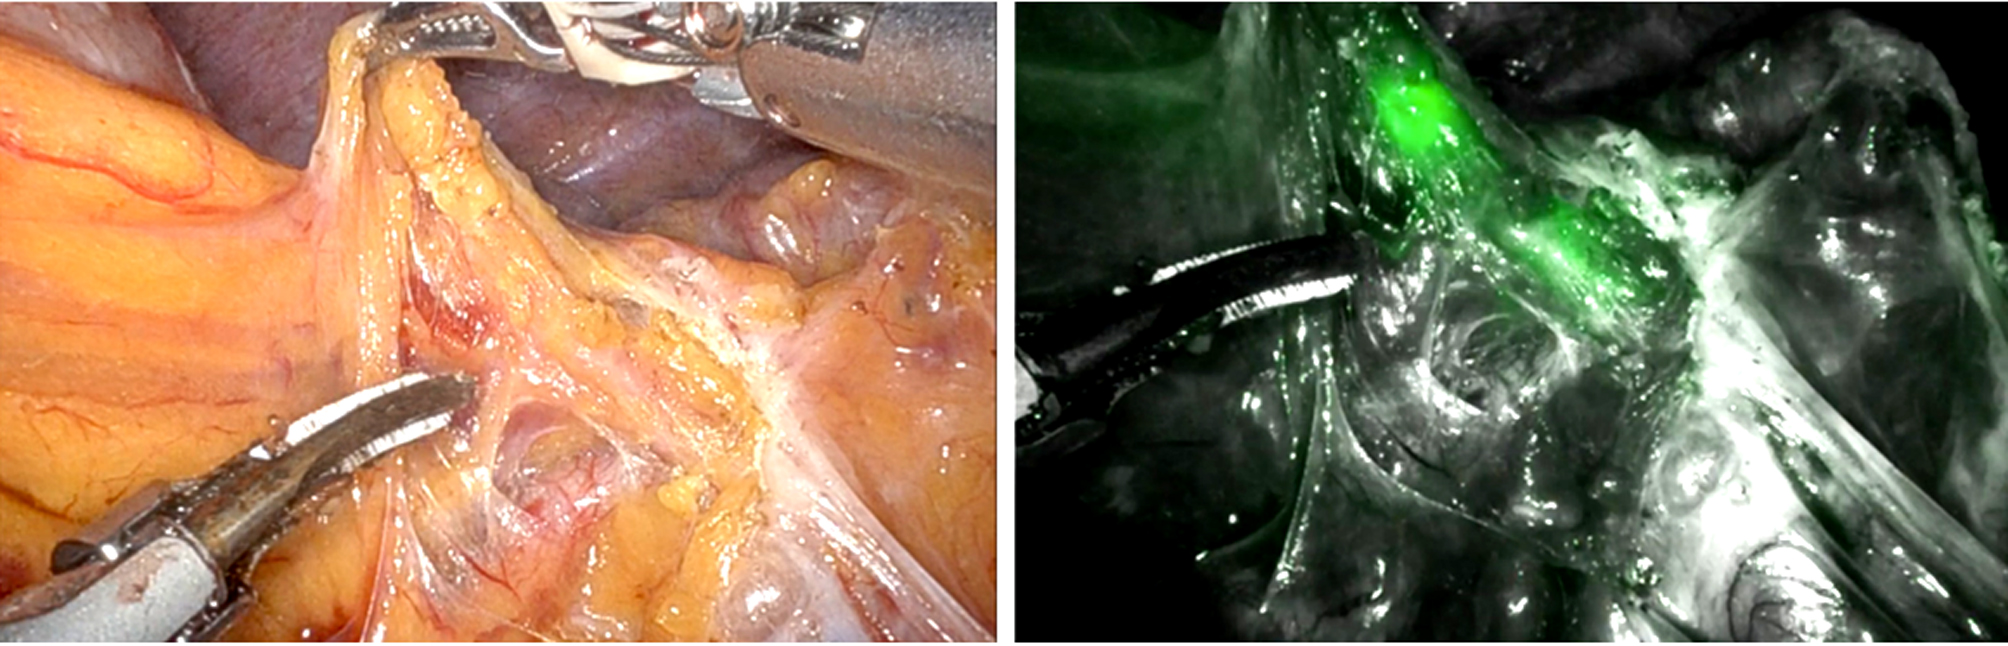

During minimally invasive gastric cancer surgery for lymphatic identification, fluorescent lymphography (FL) utilizing indocyanine green under near-infrared imaging is considered the most effective tool for lymph node identification (23). The splenic hilar area presents the most difficulties when undergoing lymphadenectomy during total gastrectomy beyond the stomach. A relatively high therapeutic index and rates of splenic hilar lymph node metastases of 14.1% and 19.2% in the RGC following partial gastrectomy for malignant and benign disease, respectively, confirm the recommendations for splenic hilar area dissection (24). Because fluorescent lymph nodes would be easily visible in the dissected area and the chance of leaving lymph nodes there would be minimized, FL allowed for the intraoperative evaluation of the lymphadenectomy's quality (25). FL is also recommended when fluorescence is present as a helpful tool to perform good-quality lymphadenectomy near the splenic hilum during complete gastrectomy for primary gastric cancer (fig. 2). FL for RGC is a potential method for completion gastrectomy because it allows for complete splenic hilar area dissection (26-27).

Figuri 2 - (a) Distal splenic artery area in remnant gastric cancer, white-light image; (b) fluorescent LNs along the distal splenic artery, fluorescent-light image